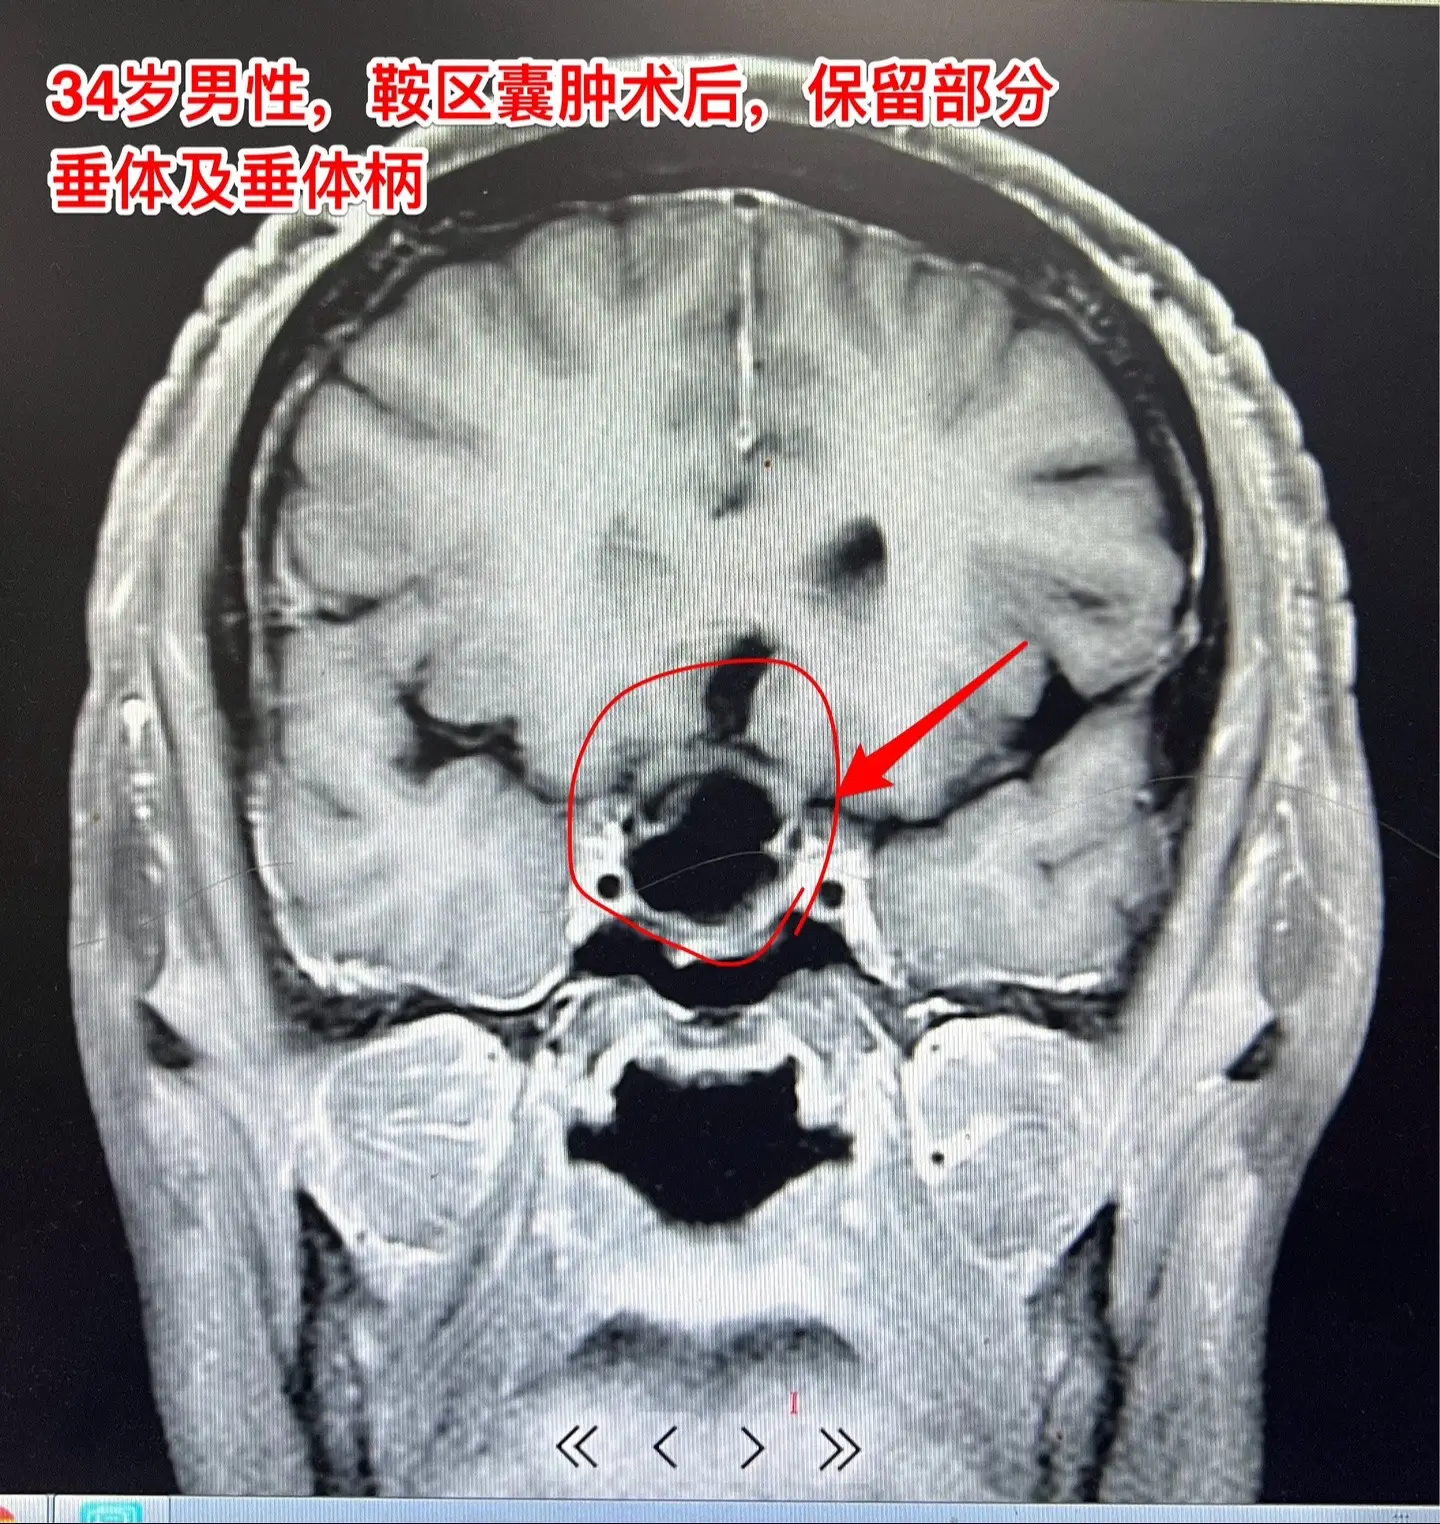

34岁男性视力下降、三个月体重下降30斤。34岁山东滕州男性,视力下降...